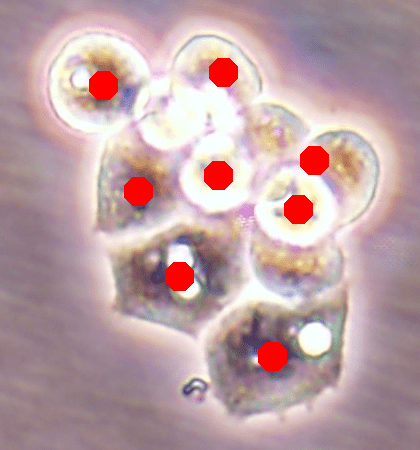

Before the advances in deep learning, the traditional approach for cell detection/segmentation is to employ low-level handcrafted features, reflecting color, edge, and shape characteristics of cells. This approach has given promising results when the features are defined properly, as a good representation of the visual cell characteristics. On the other hand, these characteristics may change from one cell type to another (see Fig. 1) and new features need to be defined to meet the cell characteristics of a new type. Additionally, when there exists heterogeneity in the visual characteristics of the same cell type, using a single model may not be sufficient to detect all cells of this type, particularly for cancer cells which are exploited more in high throughput screening.

![]() |

| (a) | (b) | (c) |

We test our DeepDistance model on three datasets, each of which consists of live cell images of a different cell line. They are the CAMA-1, MDA-MB-453, and MDA-MB-468 human breast cancer cell lines. The images in all datasets were acquired at magnification and pixel resolution. An example image from each dataset is shown in Fig. 1. As seen in this figure, cells might be visually different within and across different cell lines.